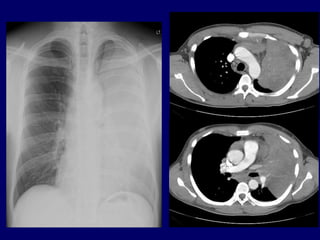

◙ A 52-year-old woman presented to her

primary care physician with a several-week

history of nonproductive cough, mild

dyspnea, chest tightness, and wheezing

◙ A chest X ray was done.

Case 2

What is the MOST LIKELY

diagnosis?

A. Pulmonary edema.

B. Pneumonia.

C. Atelectasis.

D. Mediastinal mass.

E. Left apical pneumothorax.